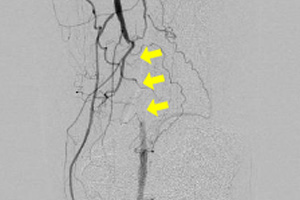

下肢動脈(浅大腿動脈)造影検査

治療前